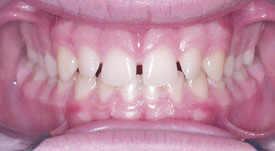

Crowding Lower